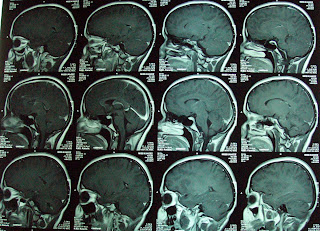

This 17 years old lady presented with with headache& vomiting since 6 months, ataxia,diplopia,diminished vision since 2 months.On MRI there was large

Post. fossa mass and hydrocephalus. She was operated for Rt.V.P.Shunt and tumor

was debulked. Histopathology was consistent with Ependymoma.

Gamma knife Radiosurgery done for residual tumor. 31 cc volume treated with 12 Gy at 50% isodose line.

Follow up MRI at 8 months showed complete disappearance

of the residual tumor as can be seen in following images.